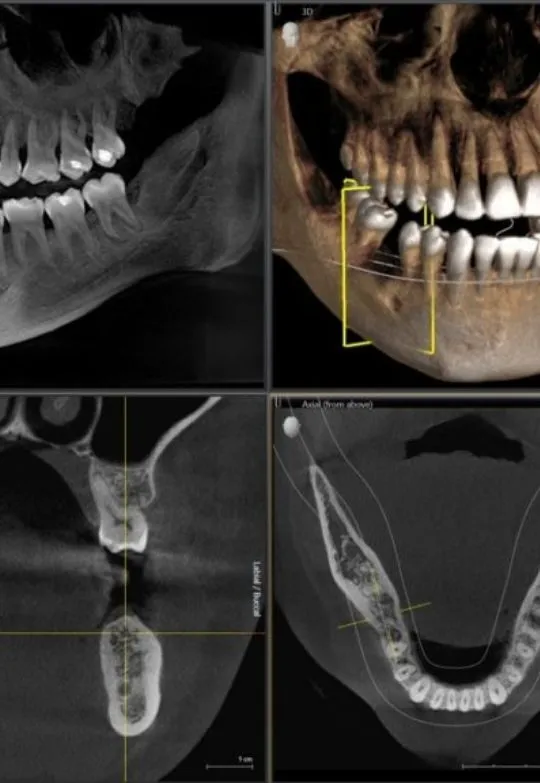

At Palermo Village Dental, CBCT (Cone Beam Computed Tomography) technology provides detailed 3D images that allow Dr. Blair to evaluate your teeth, jaw, bone, and surrounding structures with remarkable clarity.

CBCT imaging is especially valuable when planning dental implants, evaluating bone quality, diagnosing infections, and assessing complex dental conditions. By seeing the exact position of teeth, nerves, and bone in three dimensions, Dr. Blair can recommend treatment with greater confidence and accuracy. This level of detail helps reduce uncertainty and allows for more predictable, personalized care.